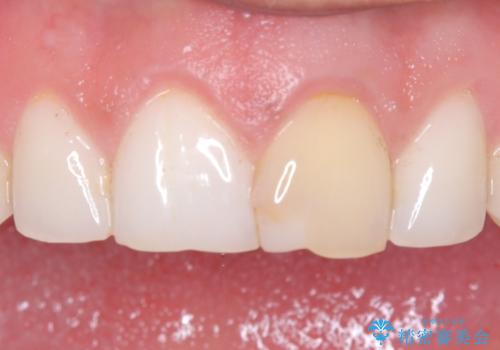

[ セラミック治療 ] 前歯の見た目を改善したい

担当医 大元洋佑